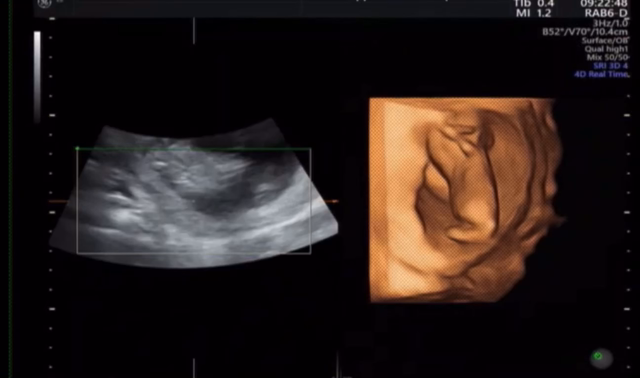

13w3d 初めての4D